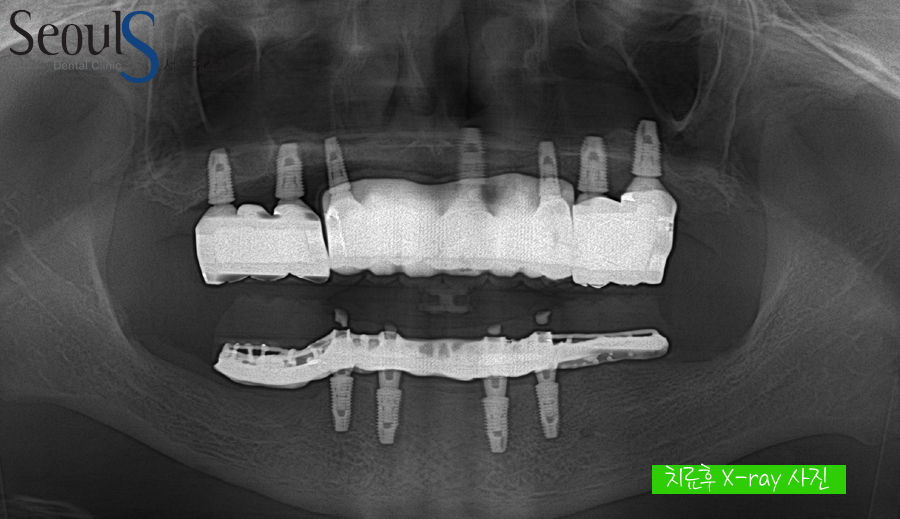

모든 치료가 끝난 후 X-ray 사진입니다

정확한 위치에 임플란트 식립, 성공적인 뼈이식, 튼튼하고 이쁜 보철물로

무치악 상태의 환자분에게 튼튼하고 예쁜 치아를 복원해드렸습니다